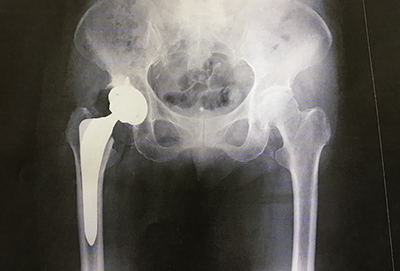

手術の方法には、自分の骨や関節を残す「骨切り術」と、股関節そのものを人工のものと取り替える「人工関節置換術」があります。

若年者を中心に基本的には骨切り術を第一選択とすることが多く、骨が壊死した範囲が大きい場合や骨が大きく壊れてしまった場合、また高齢者の場合は人工関節置換術を選択することが多いです。